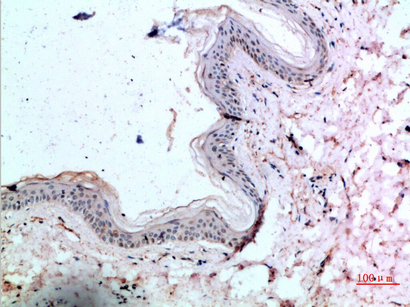

IHC-P,IF-P,IF-F,ICC/IF,ELISA

IHC-P 1:50-200, ELISA 1:10000-20000, IF-P/IF-F/ICC/IF 1:50-200